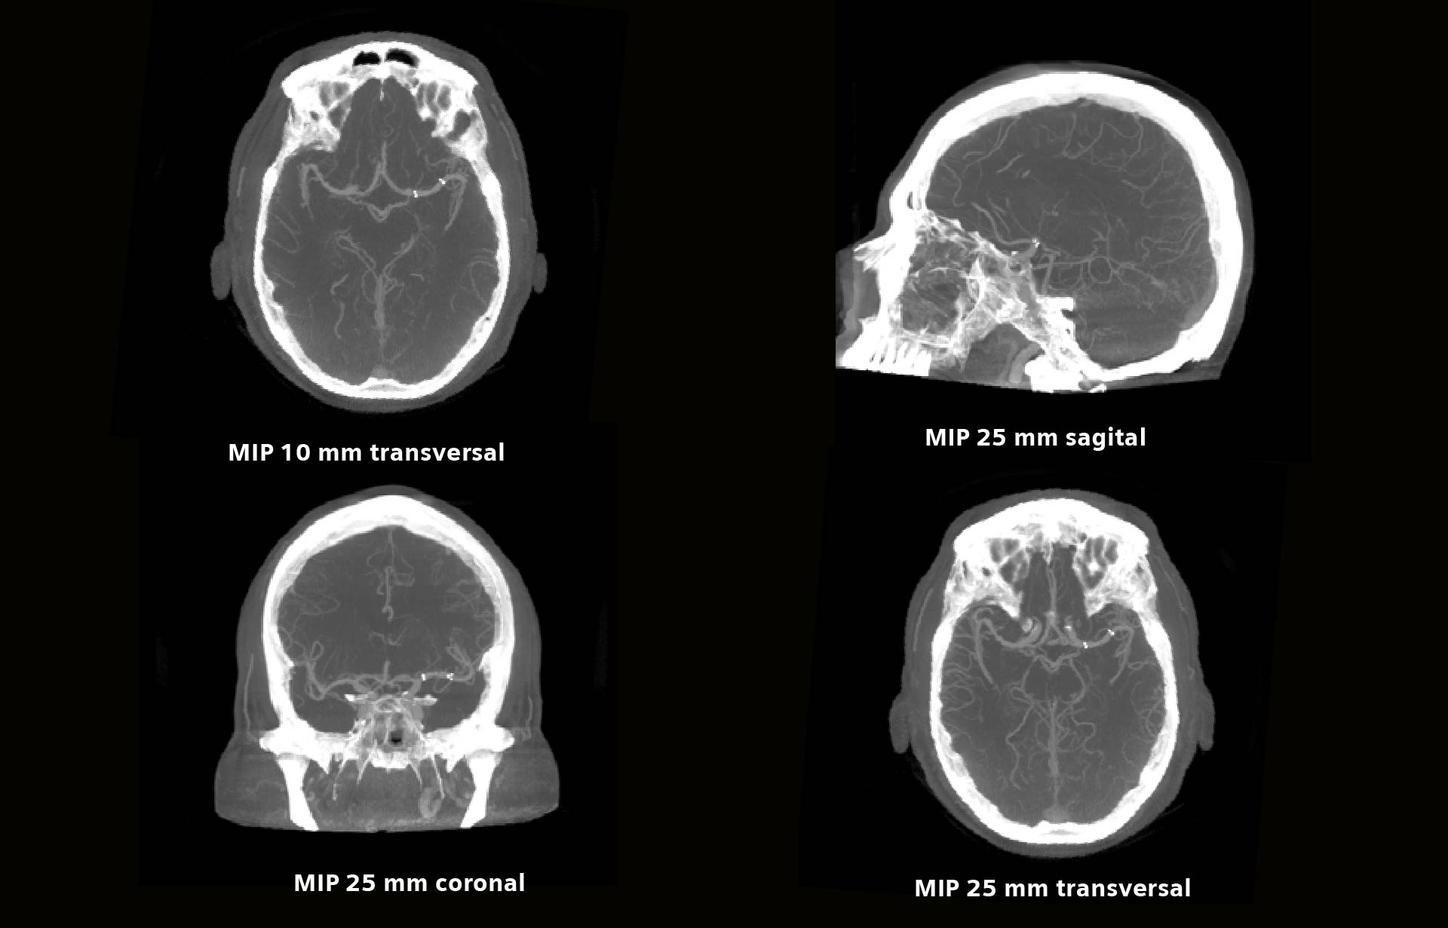

Post-trombectomía e implantación de stent

El syngo DynaCT Multiphase consta de 10 rotaciones consecutivas que dan como resultado 10 volúmenes. Comience la inyección con el inicio de la adquisición de la serie. Los primeros dos volúmenes se requieren como serie de máscara para la posible reconstrucción de los mapas de perfusión.* Los otros 8 volúmenes son series de llenado.